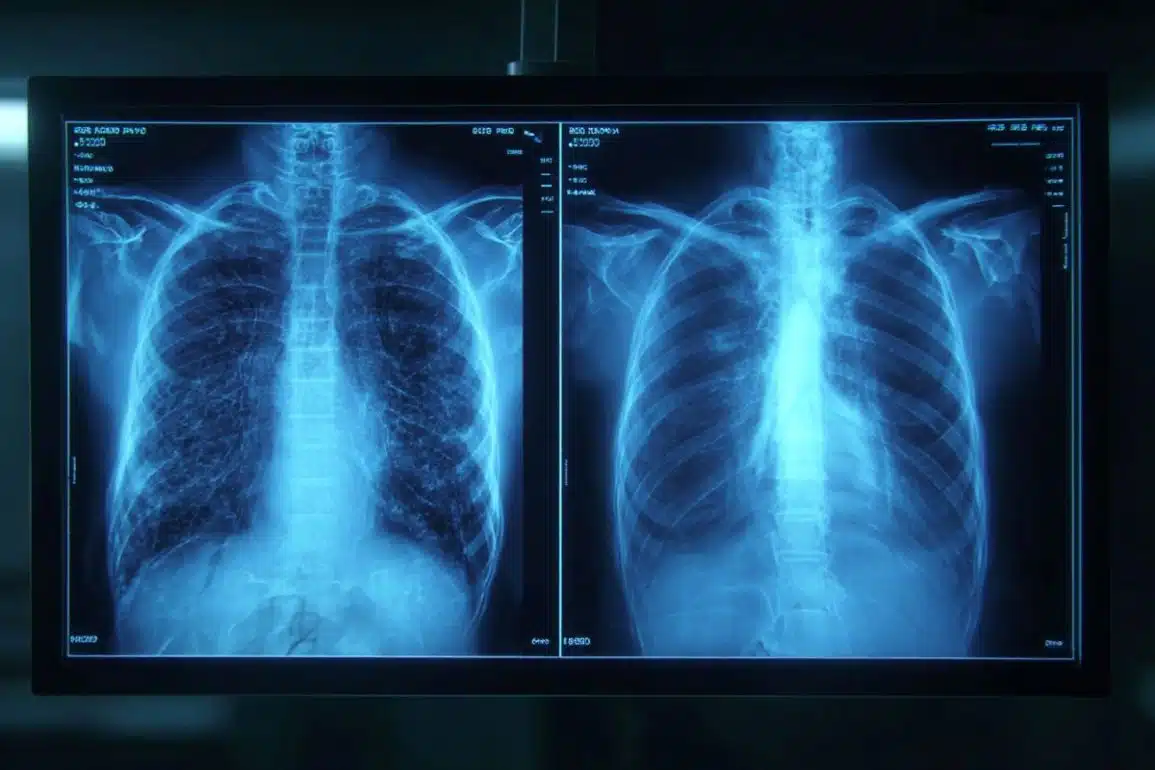

- The “Too Perfect” Tell: Deepfake X-rays often appear unnaturally symmetrical; bones are overly smooth, spines are “too straight,” and fractures look “unusually clean.”

The study identified common features of synthetic X-rays.

“Deepfake medical images often look too perfect,” Dr. Tordjman said. “Bones are overly smooth, spines unnaturally straight, lungs overly symmetrical, blood vessel patterns excessively uniform, and fractures appear unusually clean and consistent, often limited to one side of the bone.”